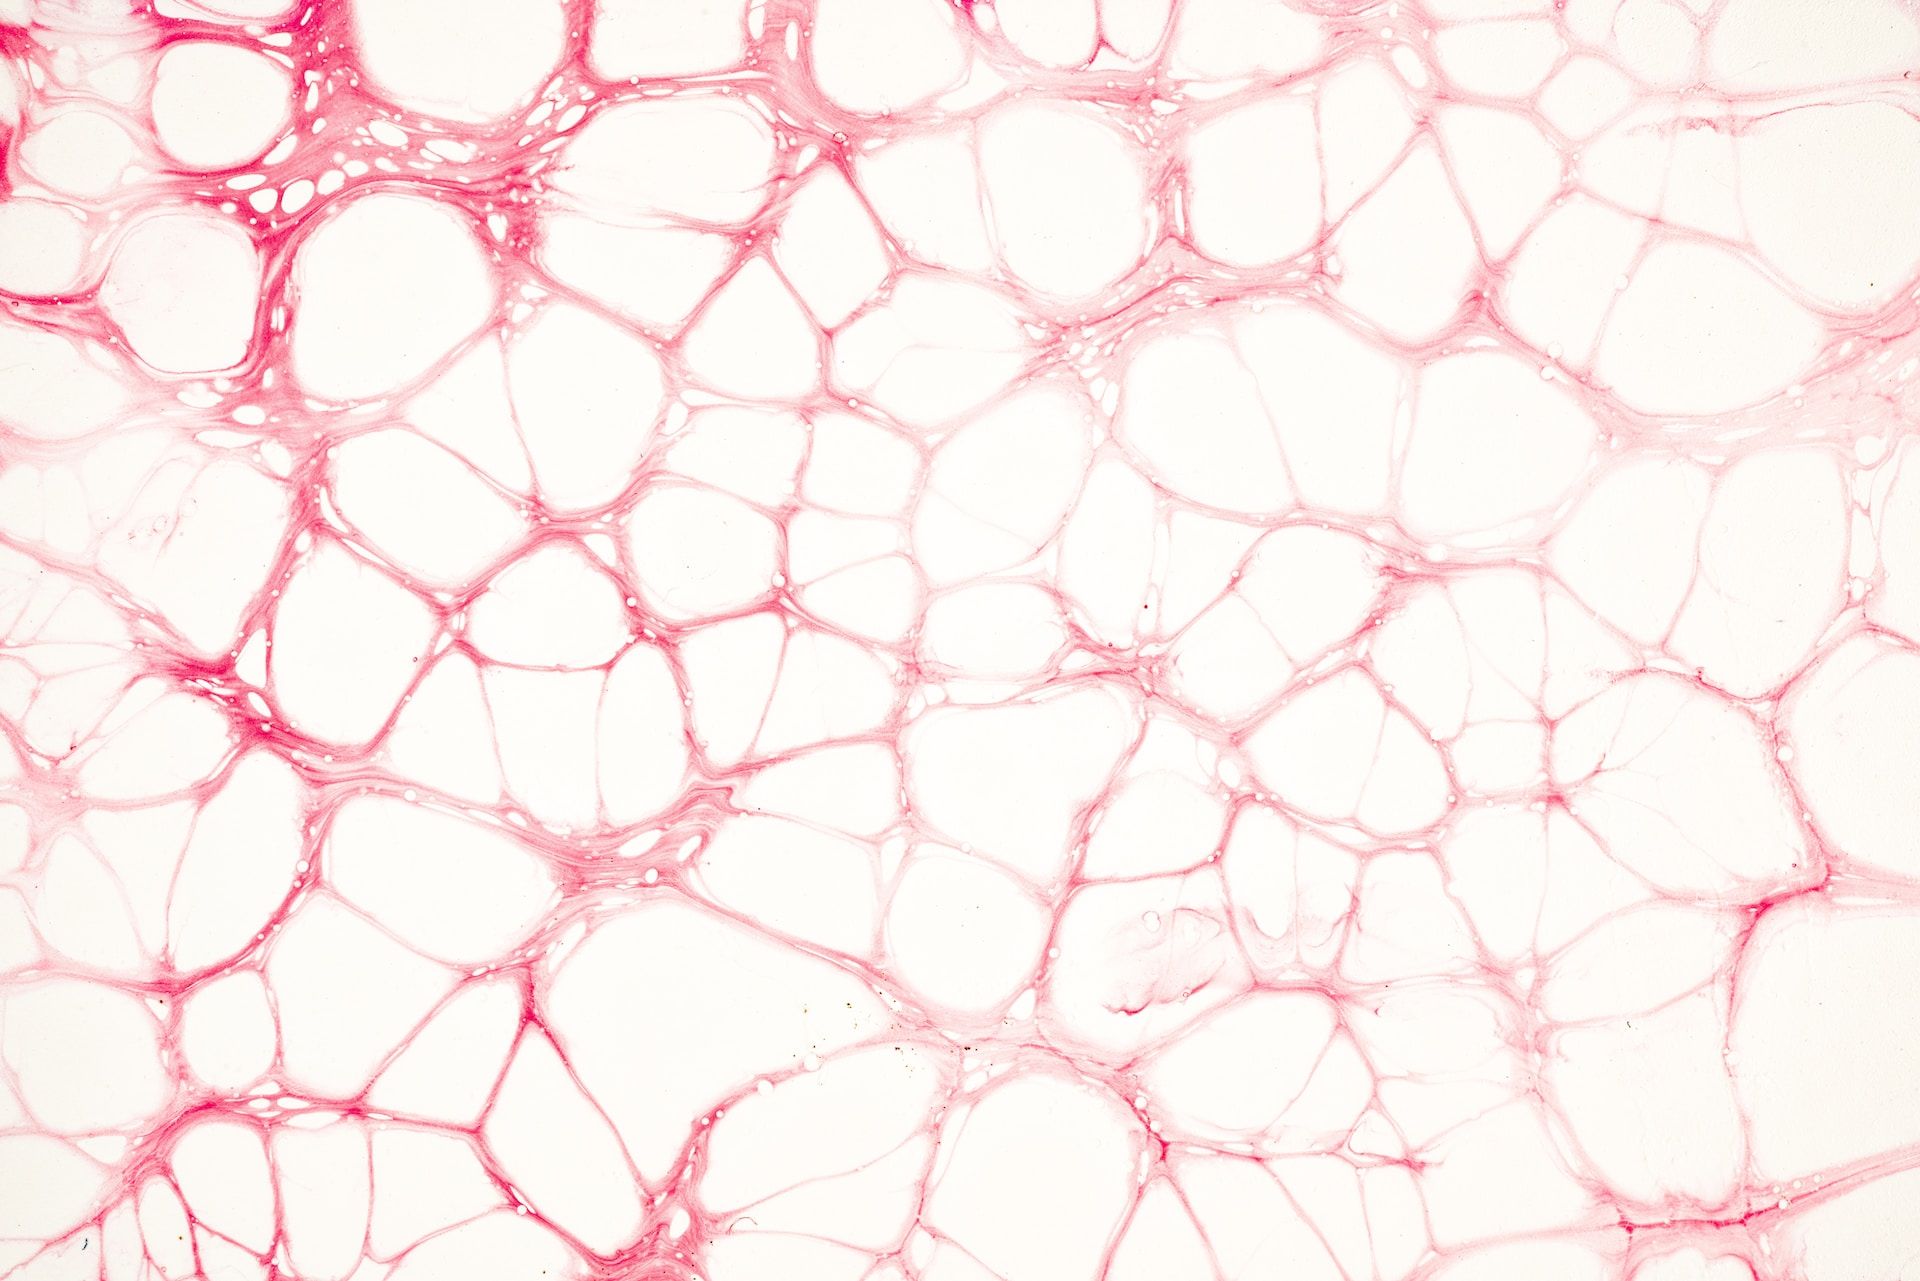

肥胖者: BMI超过24以上的族群,由于身体的皮下脂肪会阻隔散热,加上基础代谢产生的热量更多,热量就更容易积滞在体内,引起中暑。